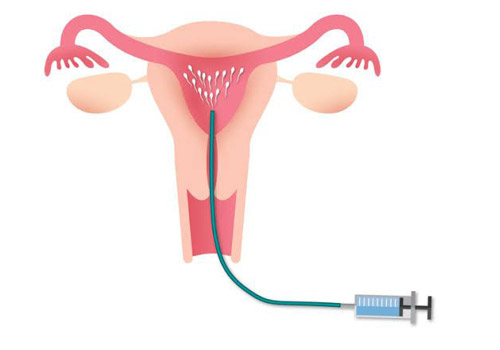

(IUI) Intra uterine insemination or Artificial Insemination

With Artificial Insemination (A), we insert the sperm we selected from a sample into the uterus. To increase chances of pregnancy, we hormonally stimulate the ovaries and control ovulation in order to know what the best time for insemination is.